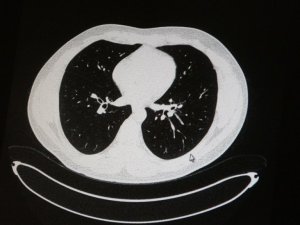

Aşılı ve aşısız olarak koronaya yakalanan 2 gencin akciğer tomografisi korkunç gerçeği gözler önüne serdi